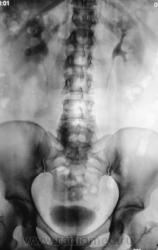

Пациент с клиникой правосторонней почечной колики направлен на рентгенологическое исследование.

В проекции среднего сегмента правой почки тень конкремента. Отсутствие признаков расширения собрательной системы правой почки.

Во-Во! И тени флеболитов в проекции малого таза.